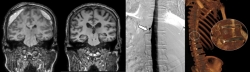

세브란스병원은 최근 DSM을 국내 최초로 도입해 이와 같은 기존 진단법의 한계를 극복했다. DSM(Digital Subtraction Myelography, 디지털 감산 척수조영술)은 척수에 조영제를 주입하고 모니터 화면으로 뇌척수액의 흐름을 실시간으로 확인할 수 있다. 이를 통해 뇌척수액이 새나가는 구멍을 정확하게 찾아낼 수 있게 됐다.

DSM과 더불어 세브란스병원이 함께 진행 중인 측위 CT 척수 조영술까지, 모두 뇌척수액 정맥 누공을 진단할 수 있는 최신 기법이다.

이번에 세브란스병원을 찾은 환자들은 DSM 검사와 측위 CT 척수 조영술로 뇌척수가 새어나가는 부위를 정확히 진단·치료받고, 뇌압을 회복했으며 경막하출혈도 사라졌다. 이에 따라 환자들이 보였던 인지기능 저하와 보행장애도 모두 호전됐다.

하우석 교수는 "자발성 두개내압 저하증과 특별한 외상이 없이 발생하는 경막하출혈의 원인 중 하나였던 뇌척수액 척수 누공은 두통, 인지능력 저하 등 심각한 고통을 일으키지만, 기존 진단법으로는 원인 규명이 쉽지 않던 상황"이라며 "세브란스병원이 도입한 DSM과 측위 CT 척수 조영술로는 척수액 누출이 발생하는 지점을 정확히 찾아내 치료할 수 있다"고 말했다.